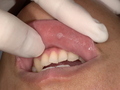

こちらは、手術後1週間程度の経過を経た下唇の状態です。手術によって粘液嚢胞が完全に除去され、傷跡もほとんど残らず、きれいに回復しました。患者様の傷跡が目立たないことが確認でき、術後の回復の良好さが表れています。

舌唇のしこりがなくなり、傷跡も残らずきれいに治癒しました。その後、再発もなく、経過は良好です。

術後1週間で抜糸を行い、以下のような経過となりました。

見た目にも自然な仕上がりで、患者様の満足度も高い結果となりました。